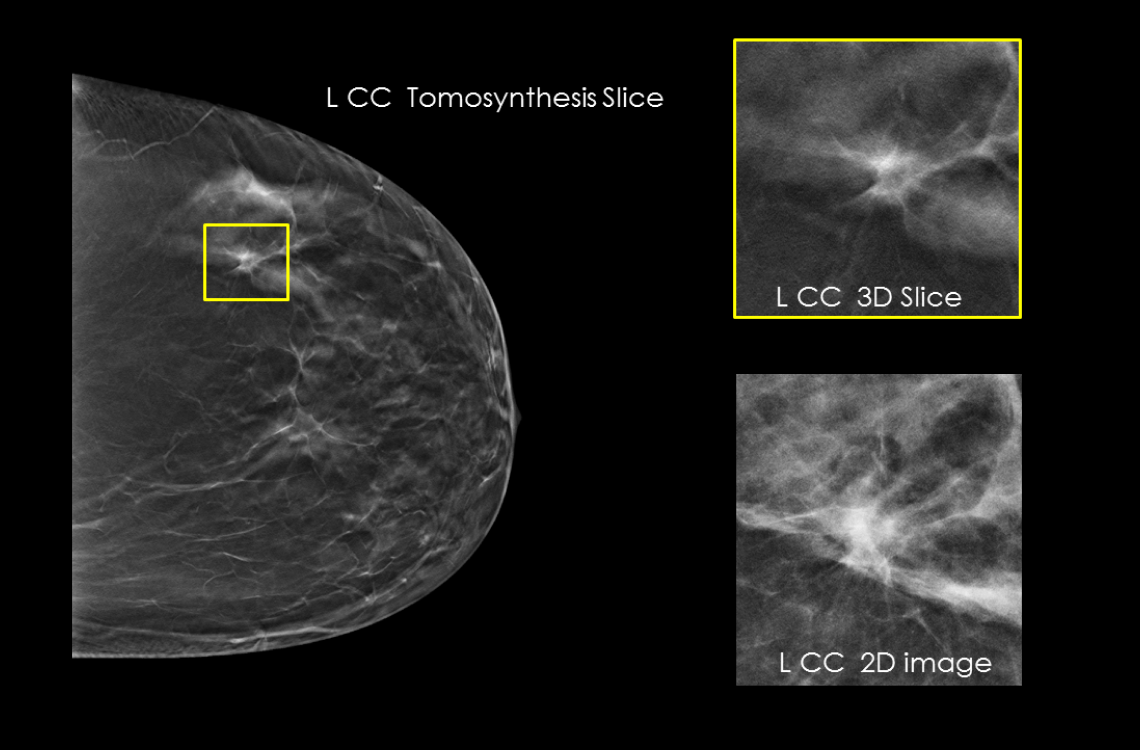

Clarity HD™ teknolojisi, Hologic’in dijital mamografi sistemlerinde yer alan yüksek çözünürlüklü 3D görüntüleme teknolojisidir. Bu sistem, meme dokusunu 70 mikron çözünürlükle katman katman tarayarak olağanüstü netlikte tomosentez görüntüleri sunar. Sonuç: daha doğru tanılar, daha az tekrar çekim ve daha güvenli tarama kararları.

Özellikle yoğun meme dokusuna sahip hastalarda, Clarity HD, dokuların üst üste binmesini önleyerek küçük kitleler, gizli kalsifikasyonlar ve diğer anormalliklerin (örneğin spiküler lezyonlar veya distorsiyonlar) daha görünür hale gelmesini sağlar. Bu da erken evre meme kanserinin tespiti açısından kritik öneme sahiptir. Geleneksel 2D sistemlerle karşılaştırıldığında, Clarity HD ile elde edilen görüntü netliği %50’ye kadar artarken, belirsiz tanılar nedeniyle istenen ileri görüntüleme oranları %40’a kadar azalmaktadır.